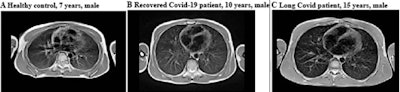

Typically, clinicians use CT to assess COVID-19's effects in adults, but the modality has "limited diagnostic value in children, where lung changes due to COVID-19 are less pronounced," the RSNA said in a statement released with the study. MRI, specifically at low field strengths (0.55-tesla), offers a way to image the lungs that does not require radiation and is able to image alveolar air tissue interfaces, the group explained.

The primary outcome the researchers assessed was structural changes of the lung parenchyma of the study participants 12 weeks after initial infection compared with MRI information from nine healthy controls who also underwent low-field MRI; the researchers then evaluated lung changes using MRI-derived functional proton ventilation and perfusion parameters (V/Q match), which measures air and blood flow to the lungs, with higher percentages of matching flow indicating better lung health.